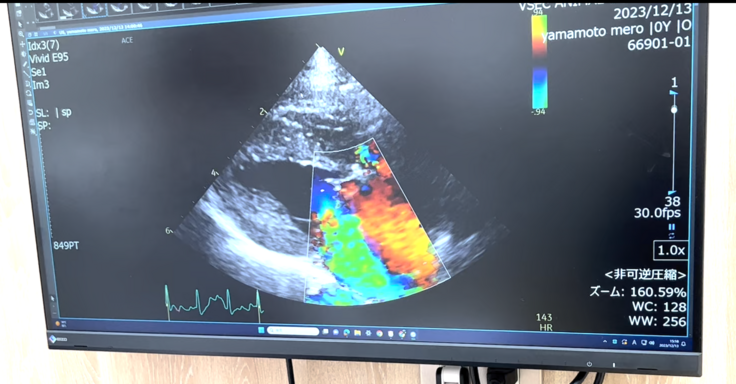

手術に向けて検査(12月13日)

大きな総合病院へ行き、メロが外科手術に適合するのか検査を行ってきました。

↑心臓のエコー、色がついている部分は弁が閉じ切らずに血の逆流が起きてしまっているとのこと。